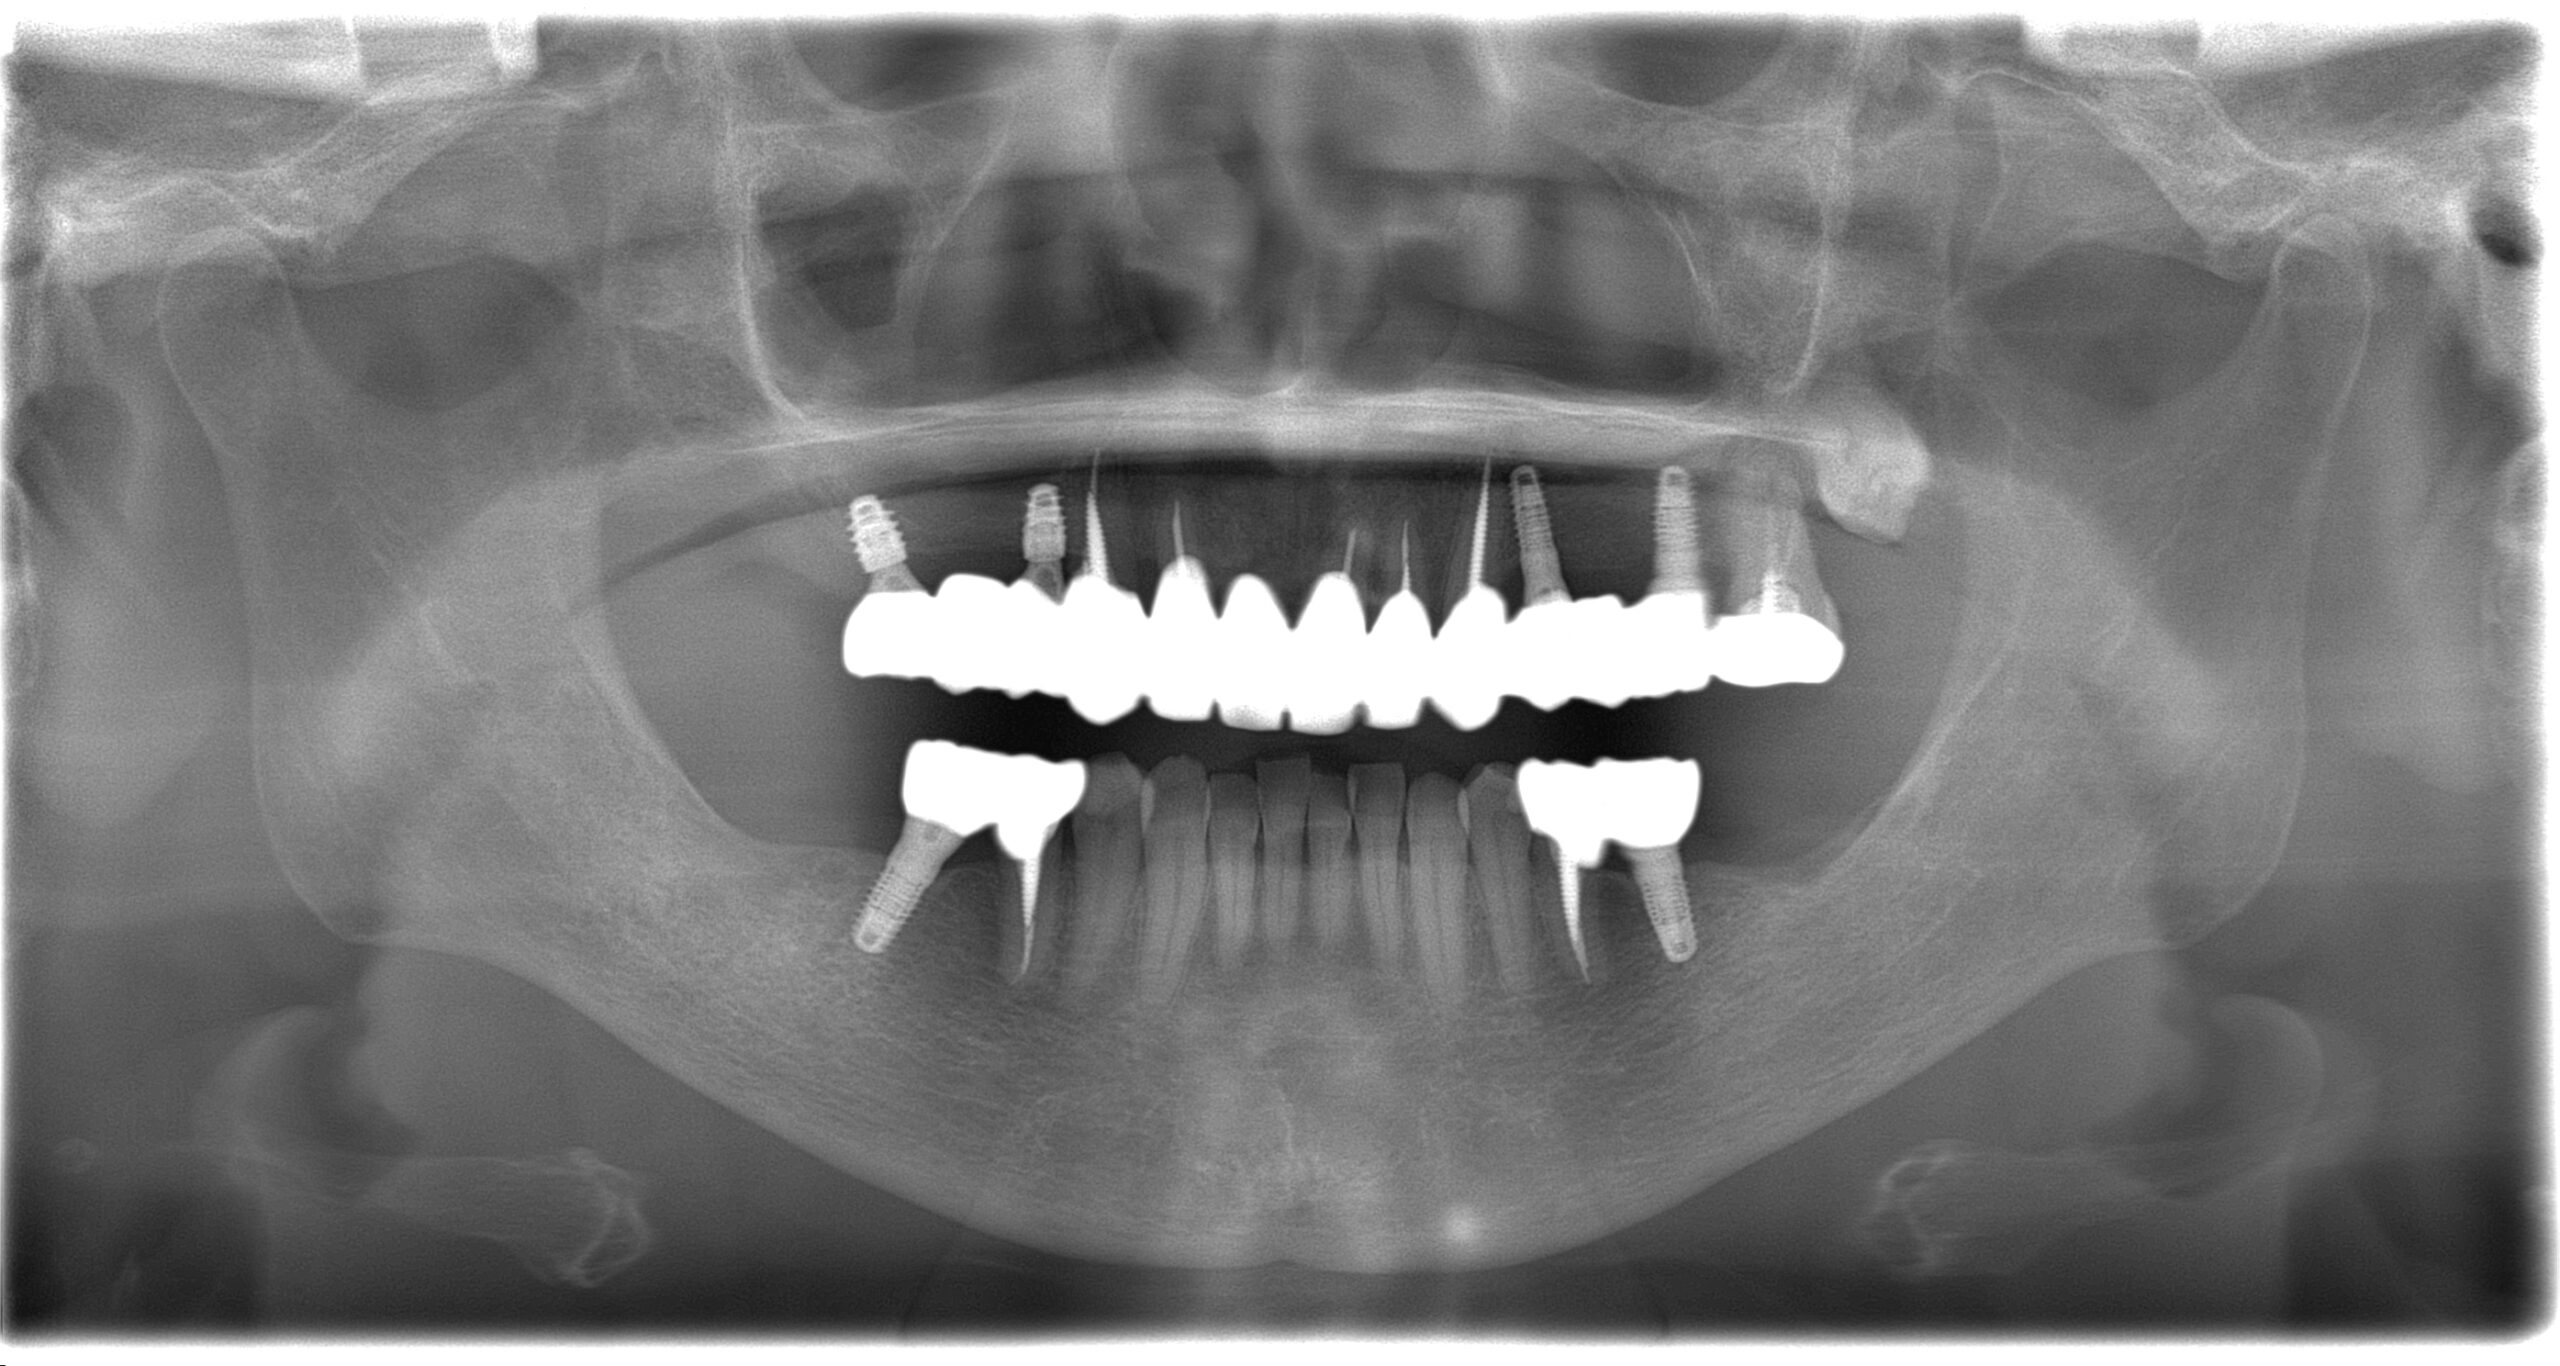

BEFORE

AFTER

主訴

全体的に見た目を綺麗にしたい。奥歯でしっかり噛みたい。

診断名・主な症状

臼歯部欠損

年齢

70歳

治療内容

インプラント埋入(右上4・6,左上4・6,右下6,左下6)

ジルコニアBr(右上3―左上3)

ジルコニア(右下5,左下5)

治療期間/

通院回数

インプラント 1年5ヶ月/13回

ジルコニアBr、ジルコニアクラウン 3ヶ月/10回

費用

インプラント: 2,552,000円

その他治療: 640,000円

合計 3,192,000円

*いずれも税込